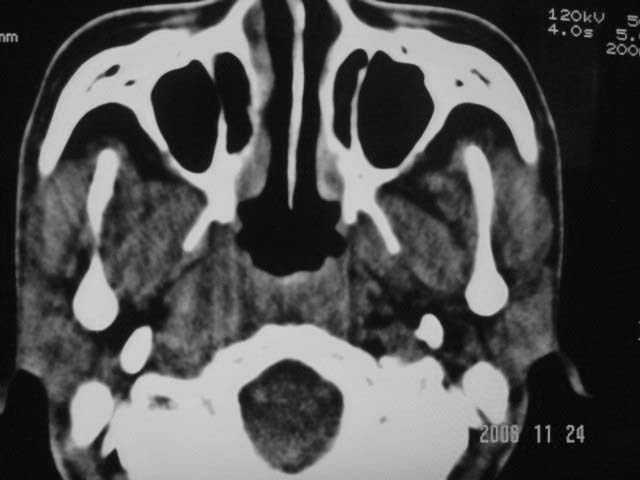

右侧鼻咽部软组织肿块,颅底骨质破坏,右侧颈部淋巴结肿大;诊断:鼻咽ca、右颈部淋巴结转移、颅底侵犯

右侧鼻口咽侧后壁不规则增厚,内可见密度不均匀性椭圆形软组织块影,边界欠清,咽旁间隙尚清.右颈部可见圆形软组织块影,鼻塞、耳鸣3个月,涕中带血2周,颈部可触及肿大淋巴结,考虑鼻咽癌,颈部淋巴转移.

右侧鼻咽后壁不规则增厚,内可见密度不均匀性椭圆形软组织块影,边界欠清,咽旁间隙尚清.右侧下方可见圆形软组织块影,双侧蝶窦呈均一高密度。

考虑:1、右侧鼻咽癌伴颈部淋巴结转移;

2、双侧蝶窦炎。

右侧鼻咽部软组织肿块,颅底骨质破坏,右侧颈部淋巴结肿大;诊断:右侧鼻咽ca伴右颈部淋巴结转移、颅底侵犯.

典型右侧鼻咽ca伴颈部淋巴结转移,中颅底骨侵蚀。

右侧鼻咽侧后壁不规则增厚,咽隐窝变钝,咽旁间隙变狭窄,见组织结节影[哨兵征],蝶骨似破坏,蝶窦内充塞软组织影,翼内外肌上分间隙模糊,右颈后三角区淋巴结肿大,右侧乳突增高气房消失。考虑鼻咽癌伴蝶窦侵犯及淋巴结转移,右侧浆液性中耳炎。其他恶性病变待排。